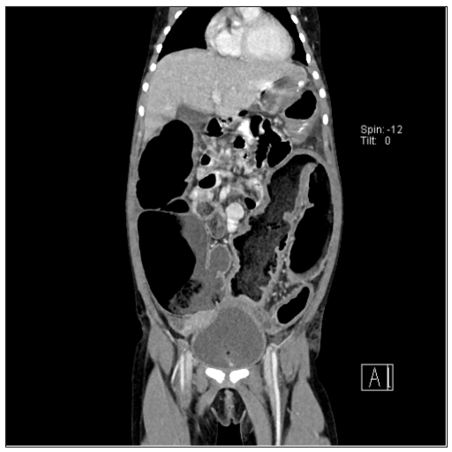

Congenital Megacolon- CT

This young girl presented with abdominal pain and constipation. Gross dilatation of the colonic loop and loops appear loaded with fecal matter. At the distal rectum there appears to be a transition between the dilated fecal matter loaded colon and empty anorectal region, which suggests a diagnosis of congenital megacolon. Hirschsprung’s Disease also known as congenital aganglionic megacolon, is an anomaly characterized by an absence of ganglion cells in the myenteric and submucosal plexuses in a variable length of bowel segment. CT finding of highly dilated proximal segments filled with feces and cone- or funnel-shaped transition segments proximal to a distal narrow segment is suggestive of the diagnosis.